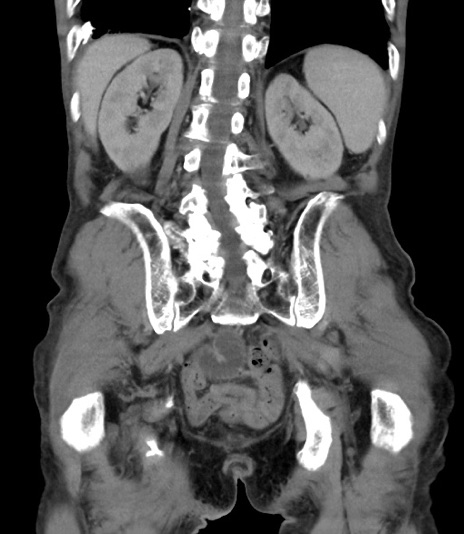

横断像

【症例】 70歳代男性

【主訴】右鼠径部腫瘤、疼痛

【現病歴】本日朝より上記主訴あり、受診。

【既往歴】膀胱癌にて膀胱全摘、両側尿管皮膚瘻

【データ】WBC 5600、CRP 0.56